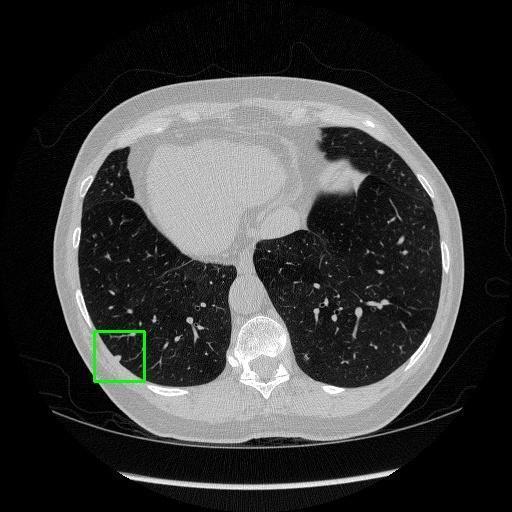

We developed an AI-based system using deep learning models for analyzing lung CT scans to detect and classify pulmonary nodules. We chose the YOLOv11 architecture for its enhanced object detection capability and adapted it specifically for medical imaging, incorporating pixel-level precision and severity classification.

Classification into three severity levels with colored bounding boxes.

Successfully built and deployed an AI model (YOLOv11) capable of detecting lung nodules in CT scans with high accuracy and real-time performance.

Designed a severity classification system that categorizes nodules into null, moderate, and severe using colored bounding boxes, assisting in rapid clinical decision-making.